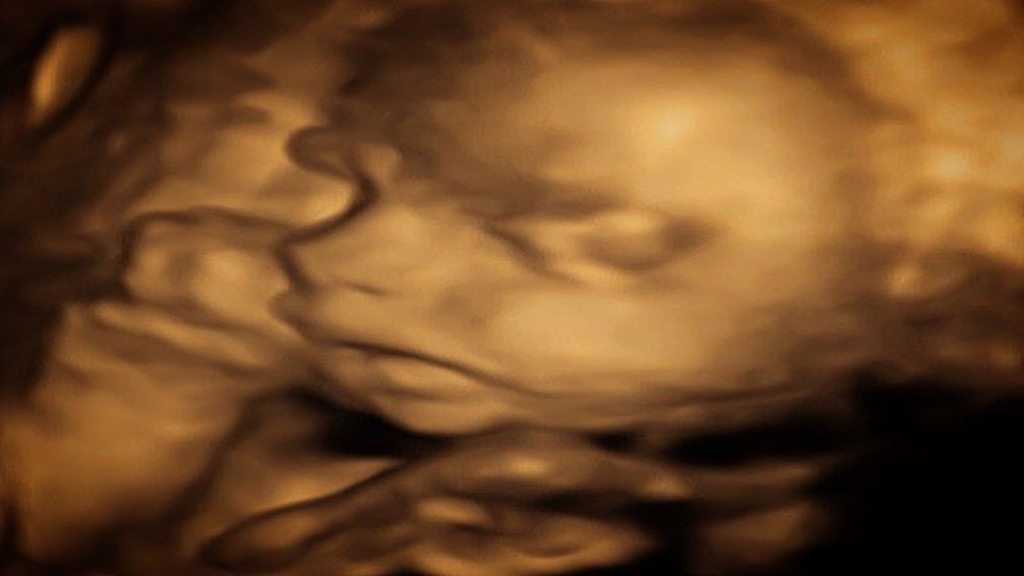

The Duke and Duchess of Sussex have announced they are expecting a baby in the Spring, but they aren't the only ones with baby news.